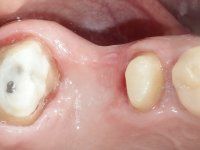

Teeth 17 and 16 were prepared for the fabrication of a 2-element Zr bridge. The impression was performed with a double mixing technique and a monolithic bridge in Zr was made in the laboratory. 4 years later, an abscess appeared in the apical area of tooth 26. It was decided to remove the bridge, remove the intra-radicular posts and retract the endodontic treatments of teeth 17 and 16. The removal of the bridge was carried out by making two cervical cavities. in the palatal area of the bridge and with a microluxator, disinsertion movements were performed. The intra-radicular posts were removed using fine drills and an ultrasound tip. The bridge was provisionally cemented and the patient was referred to a fellow endodontist for endodontic retreatment. After the retreatment, the intraradicular posts were placed again and the bridge was definitively cemented. One year later, a new abscess appears, possibly related to a root fracture. The bridge was sectioned between tooth 27 and 26 and tooth 26 was extracted and the crown of 27 was provisionally cemented. 3 months later, teeth 27 and 25 were prepared and a temporary bridge was made in dual polymerization resin. Then, an impression was made using the double mixing technique and a 3-element bridge in Zr was made in the laboratory. It was permanently cemented in the mouth with resin-reinforced glass ionomer cement.